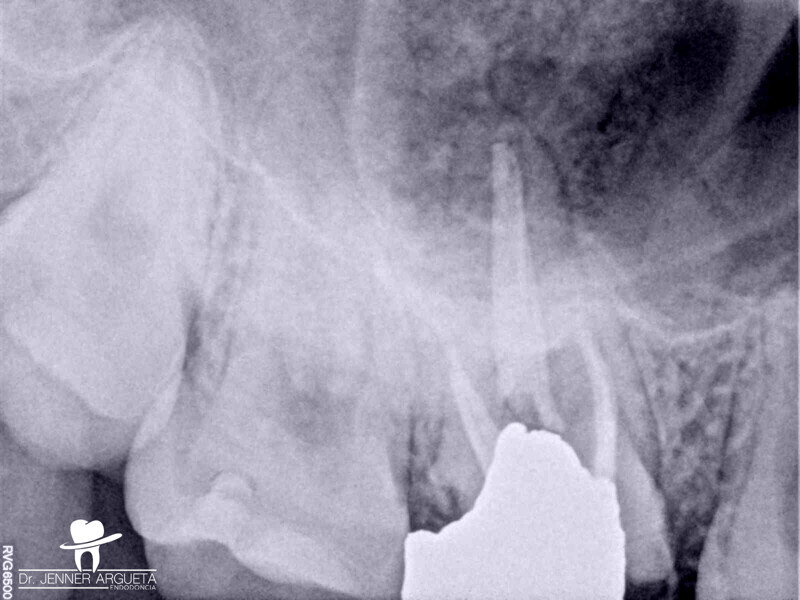

Autogenous transplantation followed by conservative root canal therapy: Three years follow-up